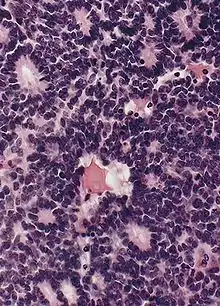

Flexner-Wintersteiner rosettes

- Neuroepithelial origin

- Tumor cells form Flexner-Wintersteiner rosettes